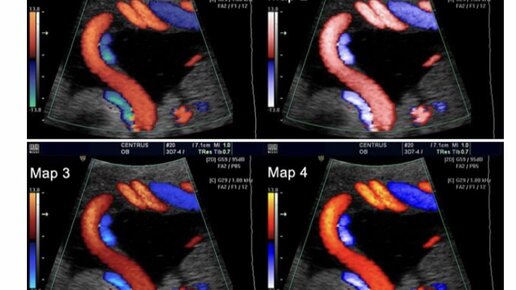

Преэклампсия представляет собой одно из наиболее серьезных и непредсказуемых осложнений беременности, затрагивающее до 8% всех беременностей по всему миру. Это мультисистемное расстройство, характеризующееся развитием гипертензии и протеинурии после 20-й недели гестации, может привести к катастрофическим последствиям как для матери, так и для плода, если не будет своевременно диагностировано и адекватно управляемо. Традиционные методы диагностики, основанные на измерении артериального давления и...